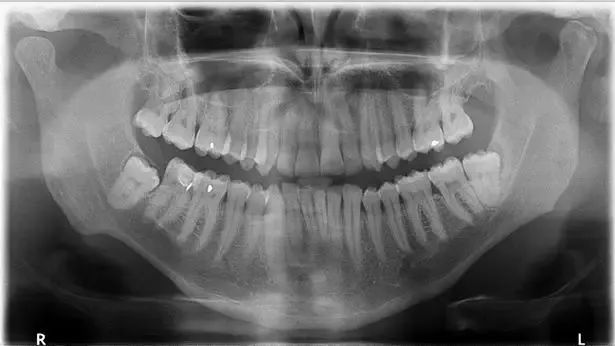

- 可能存在恒牙的先天缺失。

- 这种情况需要到医院借助X线片来判断,如果确定先天缺失,正畸医生会根据周围牙齿的排列情况选择合适时机、恰当方法进行治疗。